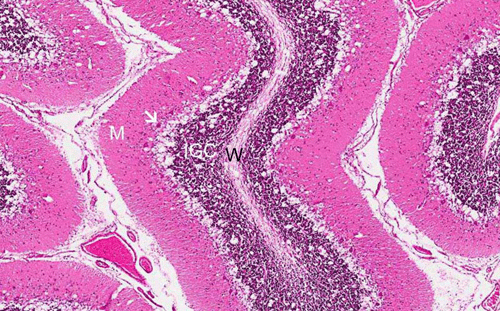

Canavan disease, HE stain: Note the impressive spongiotic gap between the molecular layer (M) and the internal granule layer (IGC). Purkinje cells are highlighted by the arrow and the white matter is labeled with "W".